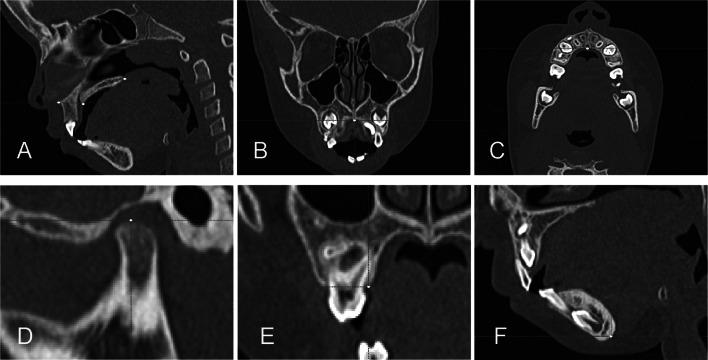

Retrospective assessment of files from 1002 children screened between 2012 and 2020 in a hospital-based mouth-breather referral center. From this universe, 15 obstructive sleep apnea children (7 females; 8 males), ages 4.1 to 8.9 years old (mean age of 5.4 years ± 1.3), who presented indications of tonsillectomy and/or adenoidectomy were selected. The complete baseline examination (T0) was carried out before T&A and a second complete examination (T1) was made 18.7-month follow-up after T&A (ranging from 12 to 30 months). Eleven patients were submitted to T&A, and four patients had indications but did not receive authorization for surgery from the public health system. According to the protocol of the outpatient clinic for OSA patients, Doppler echocardiography, polysomnography, rhinomanometry, and computed tomography imaging was performed at (T0) and (T1).

RESULTS

PASP decreased 16.6% after T&A. NIF increased more in T&A children (40.3%) than in non-T&A children (16.8%). The upper airway volume increased in T&A and non-T&A children, but greater volumetric gain (45.6%) was found in the nasopharynx of T&A patients. OAHI did not change in six T&A children (55%) and three non-T&A children (75%). The maxilla displaced downward and backward relative to the cranial base in six T&A children (55%) and two untreated children (50%). Nine of the T&A children (85%) and three untreated children (75%) presented extensive condylar growth and increased mandibular length. The qualitative 3D assessment showed similar morphological 3D changes in T&A and non-T&A patients.

回顾性评估了 2012 年至 2020 年期间在一家以口呼吸为基础的转诊中心筛查的 1002 名儿童的档案。从这个范围内,选择了 15 名患有阻塞性睡眠呼吸暂停的儿童(7 名女性;8 名男性),年龄 4.1 至 8.9 岁(平均年龄为 5.4 岁±1.3 岁),他们有扁桃体切除术和/或腺样体切除术的指征。在 T&A 前进行了完整的基线检查(T0),并在 T&A 后 18.7 个月(12 至 30 个月)进行了第二次完整检查(T1)。11 名患者接受了 T&A,4 名患者有手术指征,但未获得公共卫生系统的手术授权。根据 OSA 患者门诊的方案,在 T0 和 T1 时进行了多普勒超声心动图、多导睡眠图、鼻阻力测量和计算机断层扫描成像。

结果

T&A 后 PASP 降低 16.6%。T&A 患儿的 NIF 增加(40.3%)明显多于非 T&A 患儿(16.8%)。T&A 和非 T&A 患儿的上气道容积均增加,但 T&A 患儿的鼻咽部容积增加(45.6%)。T&A 组的 6 名儿童(55%)和非 T&A 组的 3 名儿童(75%)的 OAHI 没有变化。T&A 组的 6 名儿童(55%)和未治疗的 2 名儿童(50%)的上颌骨相对于颅底向下向后移位。9 名 T&A 患儿(85%)和 3 名未治疗患儿(75%)出现髁突广泛生长和下颌骨长度增加。3D 定性评估显示 T&A 组和非 T&A 组患者具有相似的形态学 3D 变化。